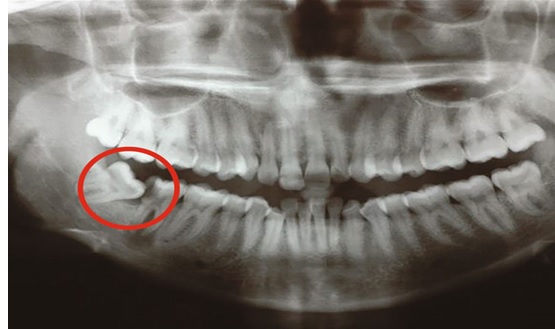

Hình thành nang hoặc tổn thương xương hàm: Trong một số trường hợp răng khôn mọc ngầm lâu ngày, quanh thân răng có thể hình thành nang răng. Nang phát triển chậm nhưng có thể làm tiêu xương hàm, gây đau hoặc làm di lệch các răng kế cận. Nếu không được phát hiện sớm, tổn thương có thể lan rộng và cần can thiệp phẫu thuật.

.jpg)

Hình ảnh nang xương hàm dưới do răng khôn mọc ngầm